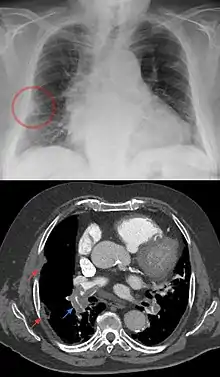

A Hampton hump in a person with a right low lobe pulmonary embolism shown in CT in the lower image (blue arrow).

Hampton's hump, also called Hampton hump, is a radiologic sign which consists of a shallow wedge-shaped opacity in the periphery of the lung with its base against the pleural surface. It is named after Aubrey Otis Hampton, who first described it in 1940.[1] Hampton's hump along with Westermark sign may aid in the diagnosis of pulmonary embolism, although they are rare and their sensitivities and interoperator reliabilities are low. If the sign is present in an image, there is a high chance that the person has a pulmonary embolism, but when the sign is absent a pulmonary embolism is not ruled out.